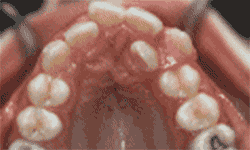

答:牙齿正畸,也就是我们口中的整牙,最主要的目标是:排齐牙齿,调整咬合。

所以首先,大多数人戴牙套的动机:牙齿不好看。这是最直观的一点,牙齿是否整齐、漂亮,是会直接影响到颜值的高低。另外,牙齿问题还可能会影响脸型,特别是侧貌,例如嘴突、地包天等。